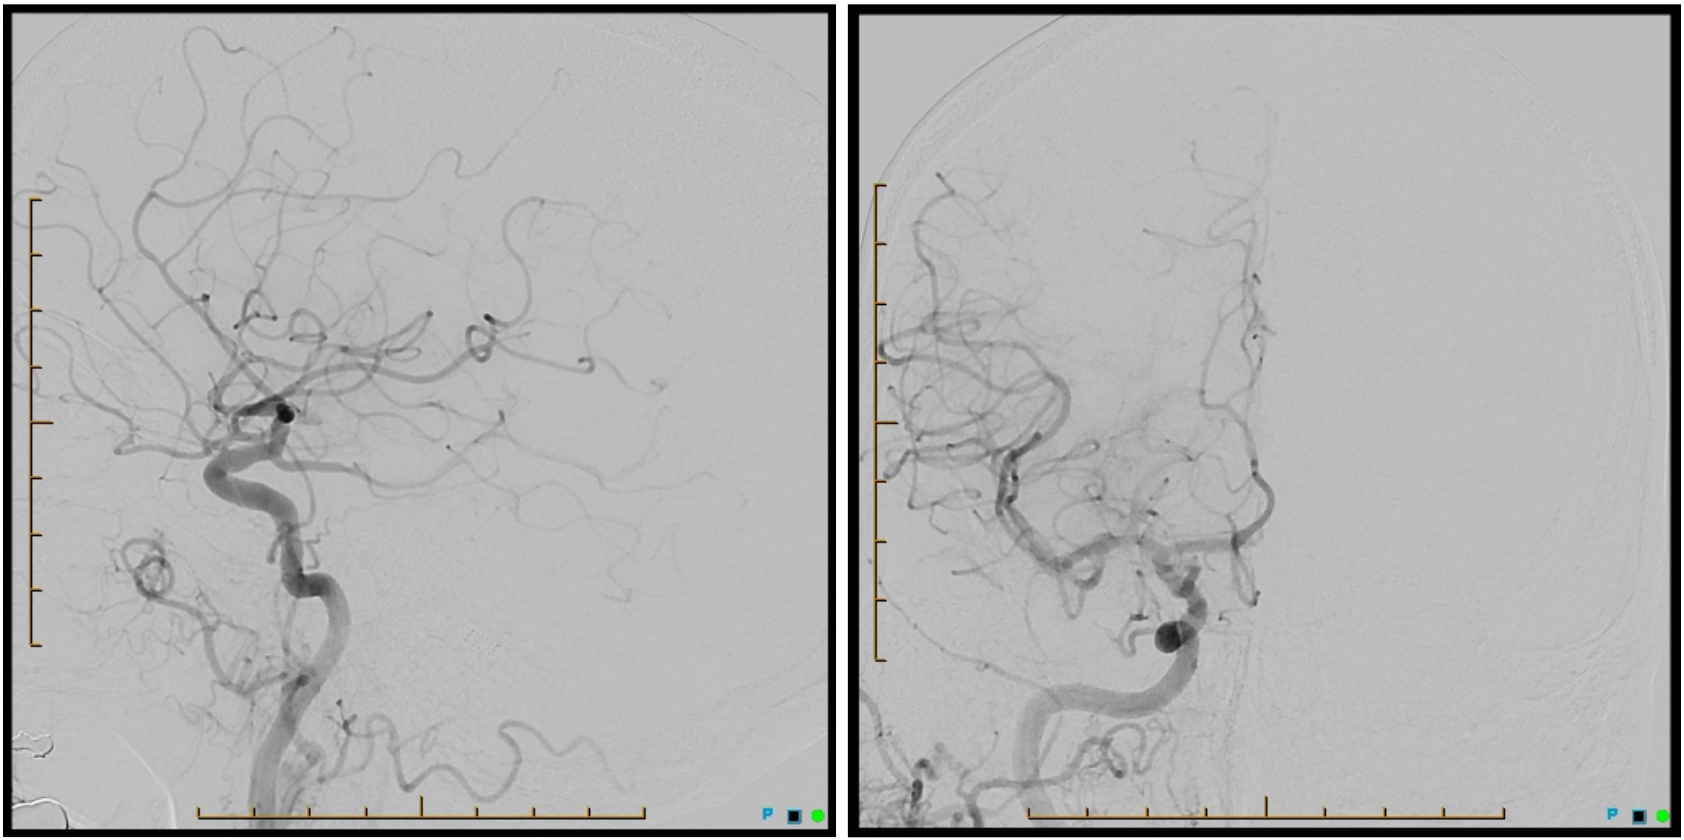

A 68-year-old man had a witnessed fall while riding his bike and was transferred to a local hospital with left hemiparesis. Computed tomography (CT) and CT angiography showed right internal carotid artery type T occlusion (Figure 1). The head CT ASPECTS score was 10.

The patient was transferred to Swedish Medical Center within 60 minutes of the previous CT, which was visualized remotely with AI technology (Figure 2).

The patient was sent DTA and a Sine Spin head CT was done (Figure 3). Thrombolysis in cerebral infarction (TICI) 3 was achieved after 1 pass (Figure 4). Time from door to recanalization was 43 minutes. Figure 5 shows the patient’s MRI after 24 hours.